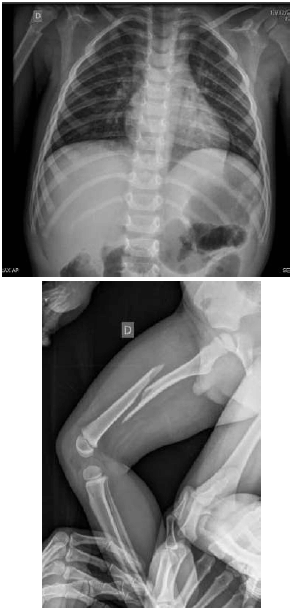

Paciente do sexo masculino, de 3 anos de idade, dá entrada no pronto-socorro infantil acompanhado pela sua mãe e pelo seu padrasto, com queixa de dor na perna por ter caído da cama há duas horas, de uma altura de cerca de 40 cm. Relatam que a queda não foi presenciada. Mãe nega qualquer antecedente prévio ou outras idas ao pronto-socorro. Em relação a outros sintomas, relataram que o paciente está com quadro de infecção de vias aéreas superiores há 2 dias, sem febre. Ao exame, o paciente revela-se choroso, não colaborativo, com dificuldade para realizar o exame físico. Foram realizadas as radiografias apresentadas a seguir.

Com base nesse caso clínico, assinale a alternativa correta.